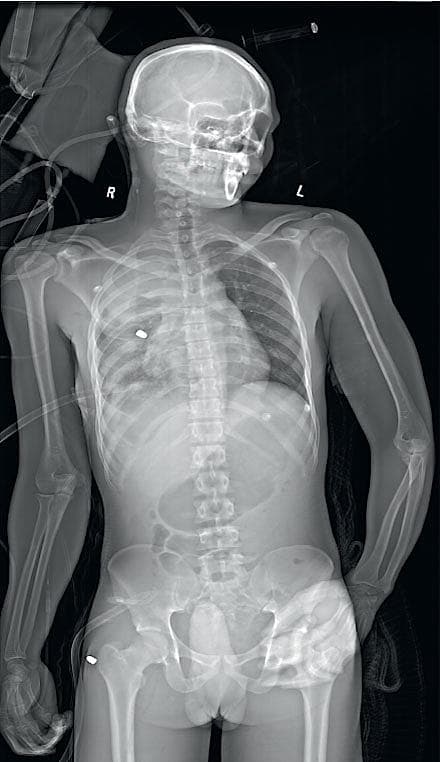

Traditionelt opdeles multitraumepatienters skader i to typer (stumpe og penetrerende). Det, der er af afgørende betydning ved multitraumer, er den energi, der er afsat i vævet ved traumet, dvs. den grad af deformering, der er opstået. Ved både stumpe og penetrerende traumer er deformationsprocessen oftest midlertidig, dvs. at vævet er deformeret under det igangværende traume, men vender tilbage til sin oprindelige plads efter traumets ophør med mere eller mindre permanente skader til følge [4].

Stumpe skader sker i Danmark oftest ved trafikulykker eller fald med større eller mindre grad af deceleration og deraf følgende påførte skader oftest på hovedet og ekstremiteterne, men for 20%’s vedkommende sker der også skader i thorax/abdomenet ved multitraumer [5, 6].

Penetrerende traumer udgør i Danmark mindre end 10% af alle multitraumer og drejer sig oftest om lavenergitraumer (forvoldt med knive m.m.) [6].

I perioder ses dog også skudlæsioner, som i Danmark oftest er mediumenergitraumer, da højhastighedsvåben sjældent finder anvendelse i det civile rum.

Under E (ekstern vurdering) afklædes og undersøges patienten, men hypotermi skal undgås, idet det forværrer den dødelige triade (koagulopati, hypotermi og acidose).